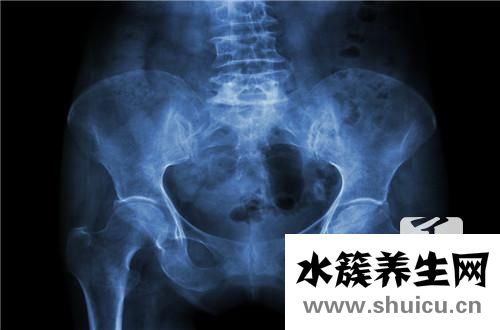

雙側骶髂關節(jié)炎是遺傳病。年齡越大越容易發(fā)展,男性患者總數(shù)遠遠高于女性患者。疾病的原因尚未確定。大部分患者臀部有疼痛,這種疼痛的抗壓強度比較高。如果生病了,可以考慮熱敷或者吃藥緩解。其次,如果比較嚴重,需要考慮醫(yī)院。醫(yī)生看了都有可能吃藥,針灸或者中醫(yī)按摩。

骶髂關節(jié)炎是關節(jié)炎中的骨關節(jié)炎的一種支系。大部分的骶髂關節(jié)炎并并不是獨立的一個病癥,只是由別的病癥造成的,如很多強直性脊椎炎炎的病人在病發(fā)前期主要表現(xiàn)為骶髂關節(jié)炎,因此 確診出骶髂關節(jié)炎還是不足的,應進一步查驗是哪種原因造成的。

雙側骶髂關節(jié)炎關鍵的臨床癥狀主要表現(xiàn)為骶髂關節(jié)位置的疼痛病癥,尤其是在疲勞或是著涼的狀況下,疼痛會更為強烈,比較嚴重的可能會影響到一切正常活動。這就是雙側骶髂關節(jié)炎的臨床表現(xiàn)。